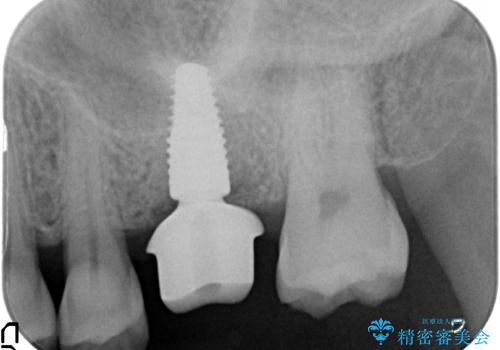

奥歯の欠損 インプラントによる咬合機能回復

- 50万円(ストローマンインプラント・骨造成・チタンカスタムアバットメント・ジルコニアクラウン)費用は治療当時の料金となります

インプラント治療について

インプラントを用いることで、隣の歯を削ることなくしっかりと噛む機能を回復させることができます。